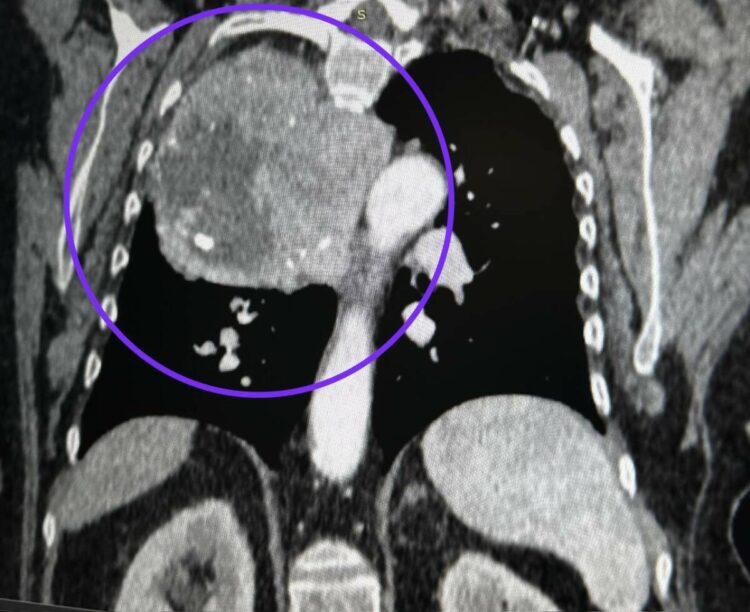

В 2017 году подобные симптомы привели к выявлению аномально увеличенной щитовидной железы, расположенной в нетипичном месте, что потребовало удаления опухоли и большей части железы. На этот раз опухоль выросла из нижнего полюса щитовидной железы и заняла треть грудной клетки.

По словам врачей, такой случай встречается в их практике впервые. Операция прошла успешно: опухоль была удалена через разрез между ребрами, на выполнение процедуры ушло три часа.